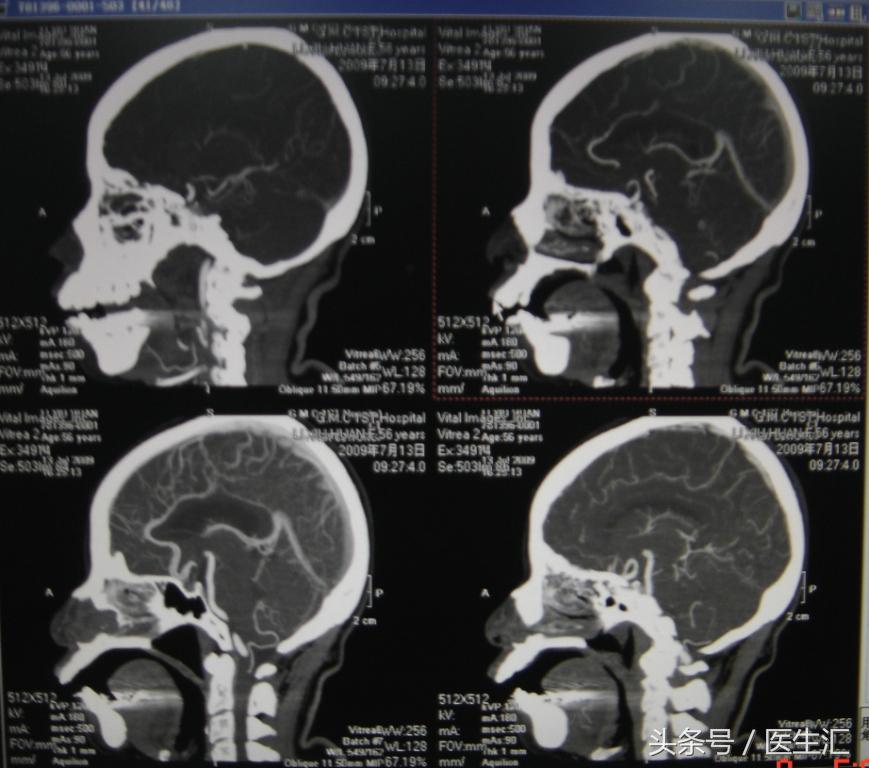

2、头颅MRI、MRA及脑血管三维重建(图12、13、14)